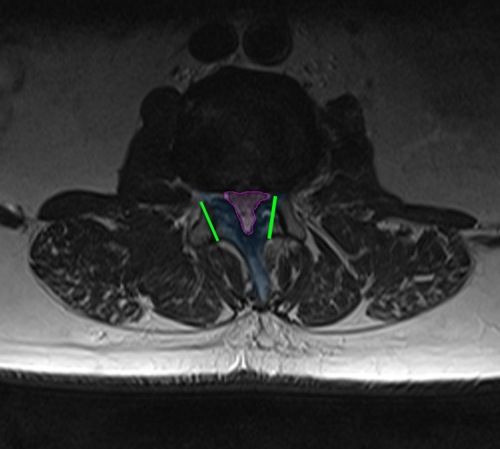

Στένωση οσφυϊκού σπονδυλικού σωλήνα (φούξια). Τα όρια της προγραμματισμένης πεταλεκτομής αναδεικνύονται με πράσινο και συμπεριλαμβάνουν το πέταλο και μέρος των μικρών αρθρώσεων (μπλέ). |

Περιγραφή Η οσφυϊκή πεταλεκτομή πραγματοποιείται με τομή στη μέση γραμμή της ράχης στο ύψος της στένωσης. Το μήκος της εξαρτάται από τον αριθμό των πετάλων που πρέπει να αφαιρεθούν. Αυτά παρασκευάζονται και αφαιρούνται. Στις εκφυλιστικές στενώσεις πρέπει συνήθως να αφαιρεθεί και μέρος των μικρών αρθρώσεων της σπονδυλικής στήλης, γιατί είναι κατά κανόνα υπερτροφικές και συνεισφέρουν στην στένωση του σπονδυλικού σωλήνα και σε πολλές περιπτώσεις εκτελείται και δισκεκτομή όταν υπάρχει και σημαντική κήλη μεσοσπονδυλίου δίσκου ως συνεισφέρων παράγοντας στη στένωση. Η αποσυμπίεση του σπονδυλικού σωλήνα ακολουθείται πάντα και από αποσυμπίεση των νεύρων στα τρήματα εξόδου τους από την σπονδυλική στήλη, μια συνοδό επέμβαση που ονομάζεται τρηματεκτομή. |